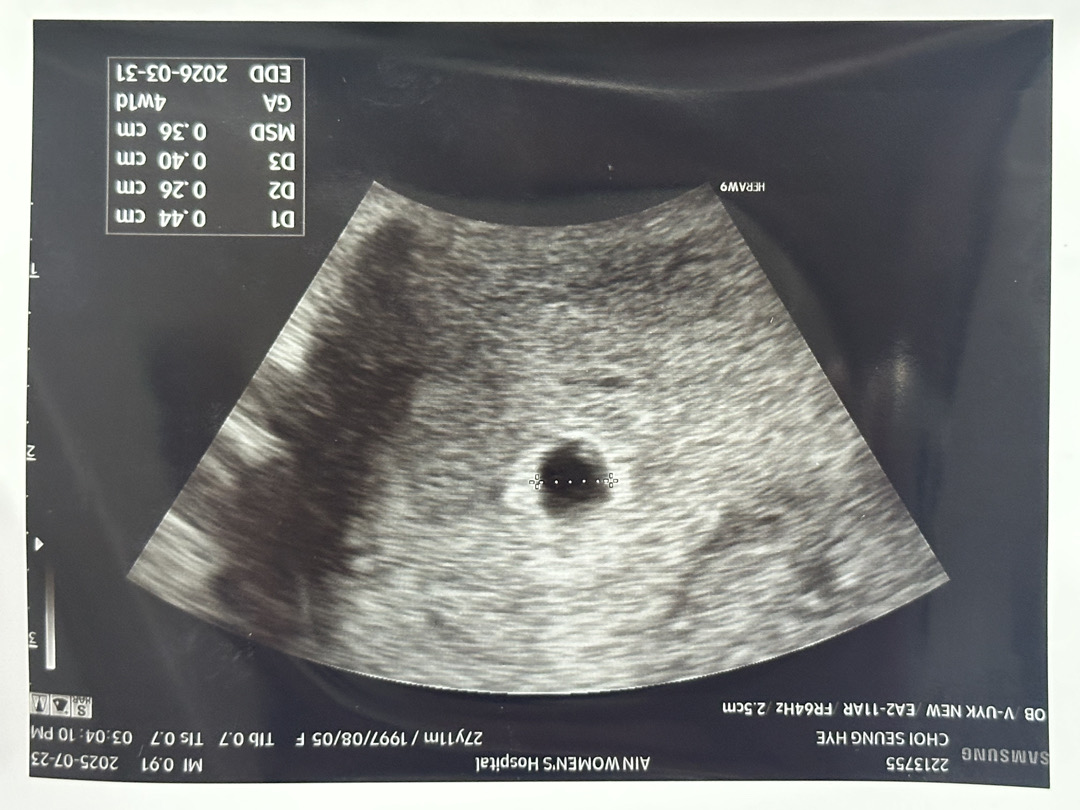

어제 처음으로 아기집을 보고 왔고 4주1일차 된거 같다구 해주셨어요! 아기집은 0.44cm 정도라고 하셨고 오른쪽 위쪽에 조그맣게 튀어나온게 있는데 아직은 너무 작아서 확신할 순 없는데 난황같다고 해주셨는데 맞겠죠?!

위쪽이 작은게 난황 맞는거 같아요!!축하드려요:)